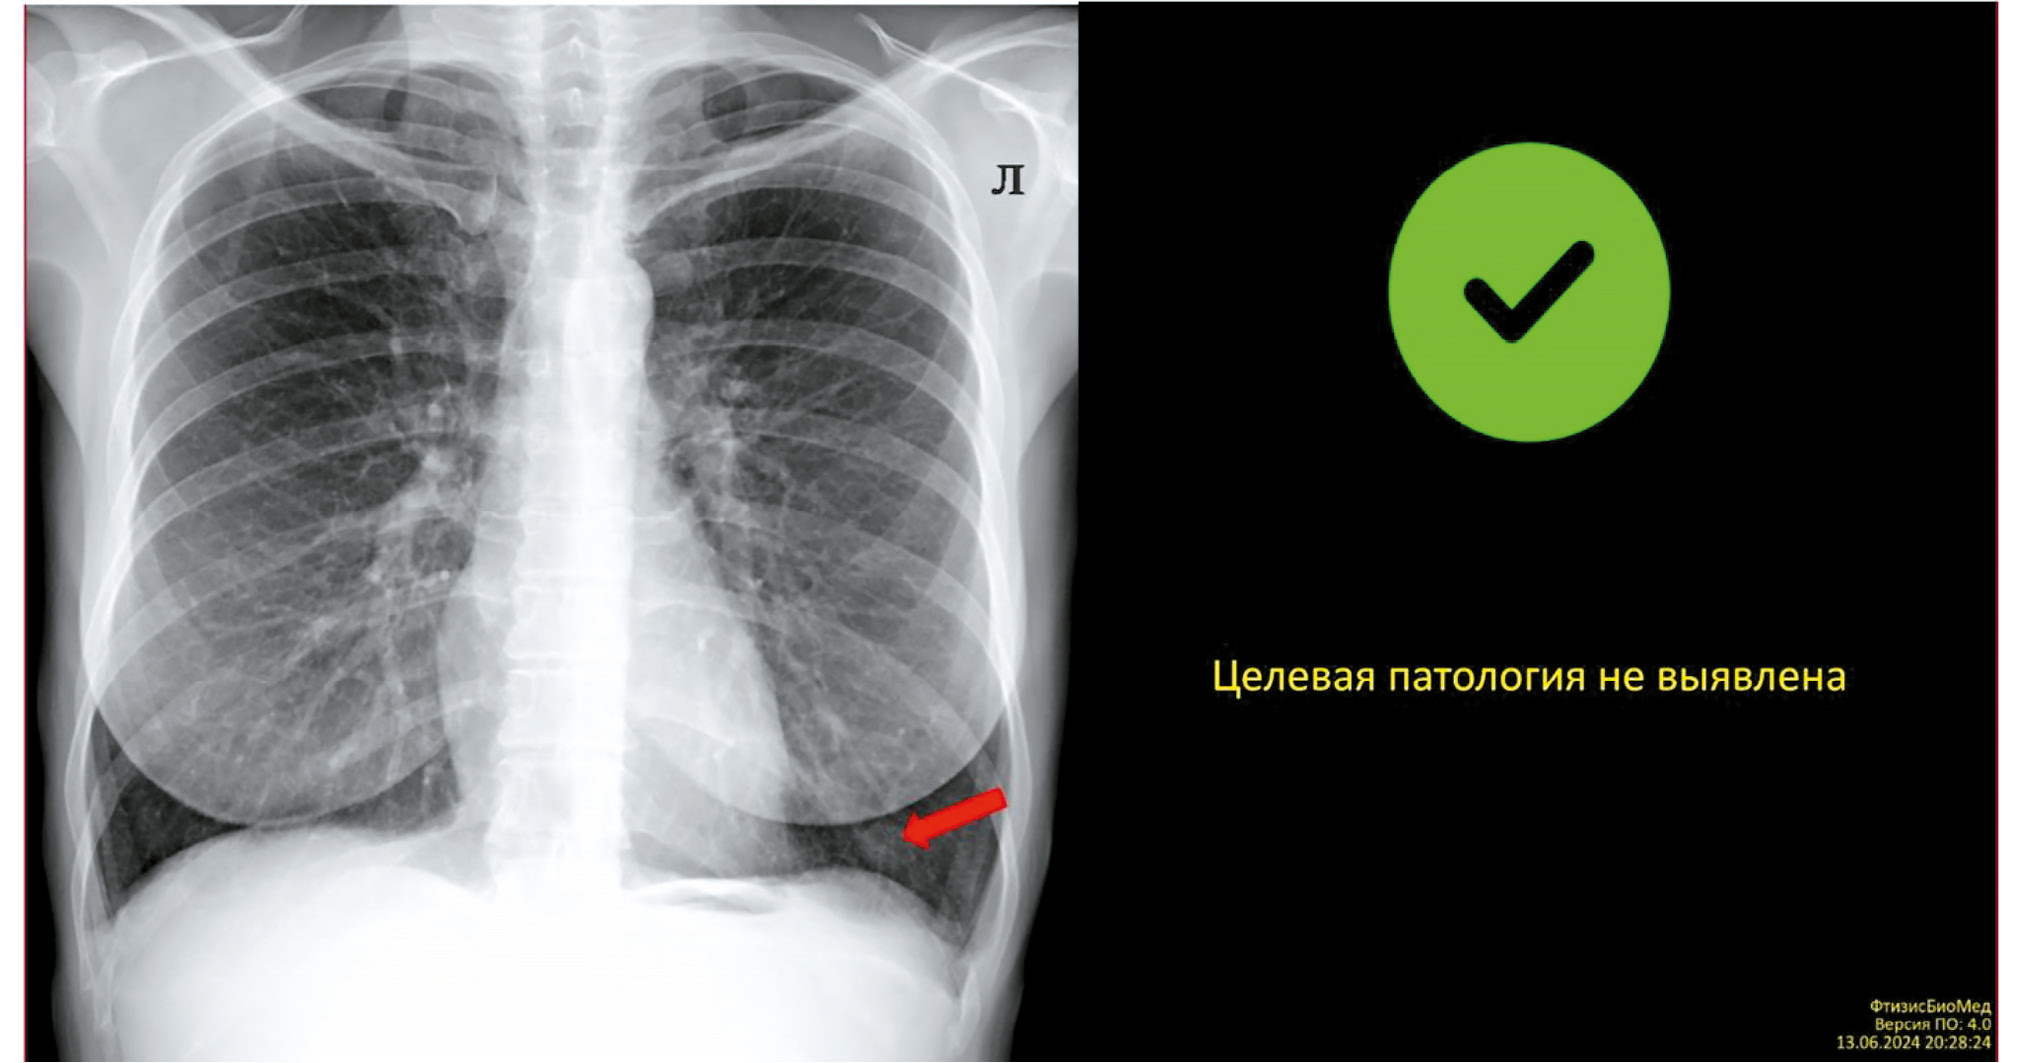

Рис. 3. Пример отображения результатов работы сервиса искусственного интеллекта в едином радиологическом информационном сервисе Единой медицинской информационно-аналитической системы г. Москвы (изображение, DICOM SR).